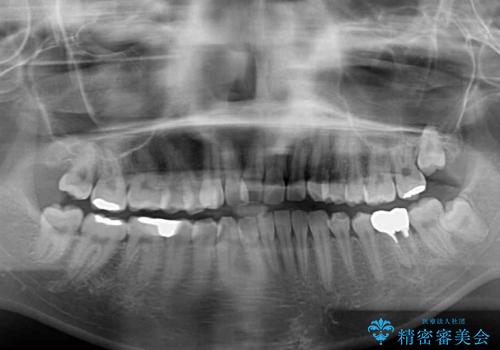

- 口の閉じにくさと割れてしまった奥歯を気にして来院された患者様です。

IPR(歯と歯の間を削る)と歯列全体の後方移動によって口元が引っ込むように設計し、インビザラインにより治療を行うこととしました。

割れてしまった奥歯は抜歯し、矯正治療中の良いタイミングでインプラントを埋入することとしました。

インプラントは、治療期間を短くすることが可能な、ストローマン社のSLActiveを使用することとしました。

上下正中がずれていたため、抜歯による矯正治療も検討しましたが、口元がそれほど突出していなかったため、非抜歯にて矯正することになりました。